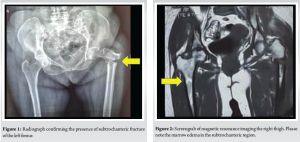

A 67-year-old female presented to the emergency department following a minor fall, reporting injury to her left lower limb. Clinical examination revealed external rotation and shortening of the left leg, with radiographs confirming a subtrochanteric fracture of left femur with features of an AFF (Fig. 1). She gave a drug history of consuming oral ibandronic acid (150 mg/month) for 7 years, as she was diagnosed with osteoporosis, indicated by a spine T-score of −3.22 on bone densitometry. In addition, the patient reported persistent right thigh pain for the preceding 3 months. Given the history of prolonged bisphosphonate use, the trivial nature of the fall, and the contralateral pain, MRI of the right femur was performed, revealing marrow edema (Fig. 2) in the subtrochanteric region, correlating with the clinical site of pain.